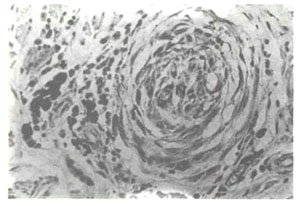

黑色体从黑色素细胞向临近角远细胞移行过程受阻。经我们多年观察发现:人体皮肤颜色主要因黑色素细胞的活性差异而不同,但皮肤颜色都不一定随黑色素细胞内黑色体增加而加深,而主要取决于黑色体从黑色素细胞向临近角远细胞移行的过程是否通畅。如皮肤炎症后色素脱失就是由于表皮细胞受损后,黑色体不能通过表皮细胞通畅排泄,而导致黑色体阻治于黑色素细胞内,使继发黑色素细胞功能减退。

临床上可见到的青色色素异常如青痣、蒙古斑、太田氏痣伊腾氏痣等,均由于真皮黑色素细胞内黑色体的生成、降解进行缓慢之故。